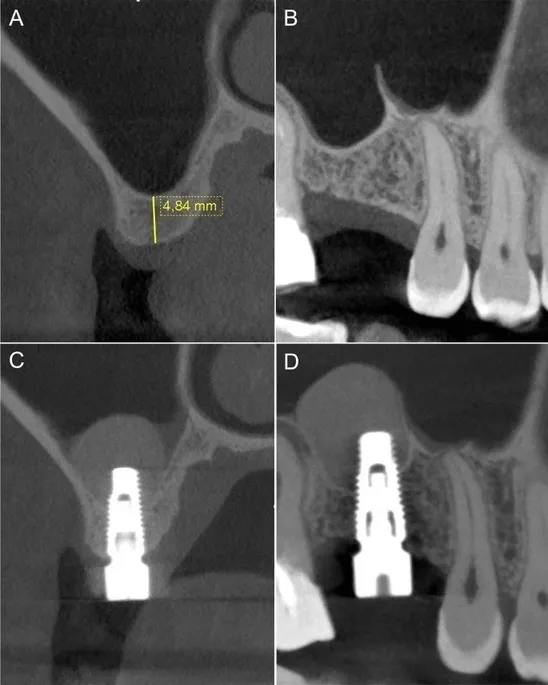

If you've been told you don’t have enough bone in the upper jaw for a dental implant, you’re not alone. In the back of the upper jaw—particularly near the molars and premolars—the bone is often too thin or insufficient due to the proximity of the sinus. This is where sinus augmentation, also known as a sinus lift, becomes an important solution.

To place a dental implant, there needs to be enough healthy bone to support it. Sometimes, the maxillary sinus (the hollow air space behind your cheekbones) is too close to where the implant needs to go, or the bone beneath it is too thin.

If you’ve been told you don’t have enough bone for an implant, a sinus lift may make treatment possible. Schedule a consultation today and we’ll walk you through your options with advanced imaging (such as CBCT scans) and a customized treatment plan.